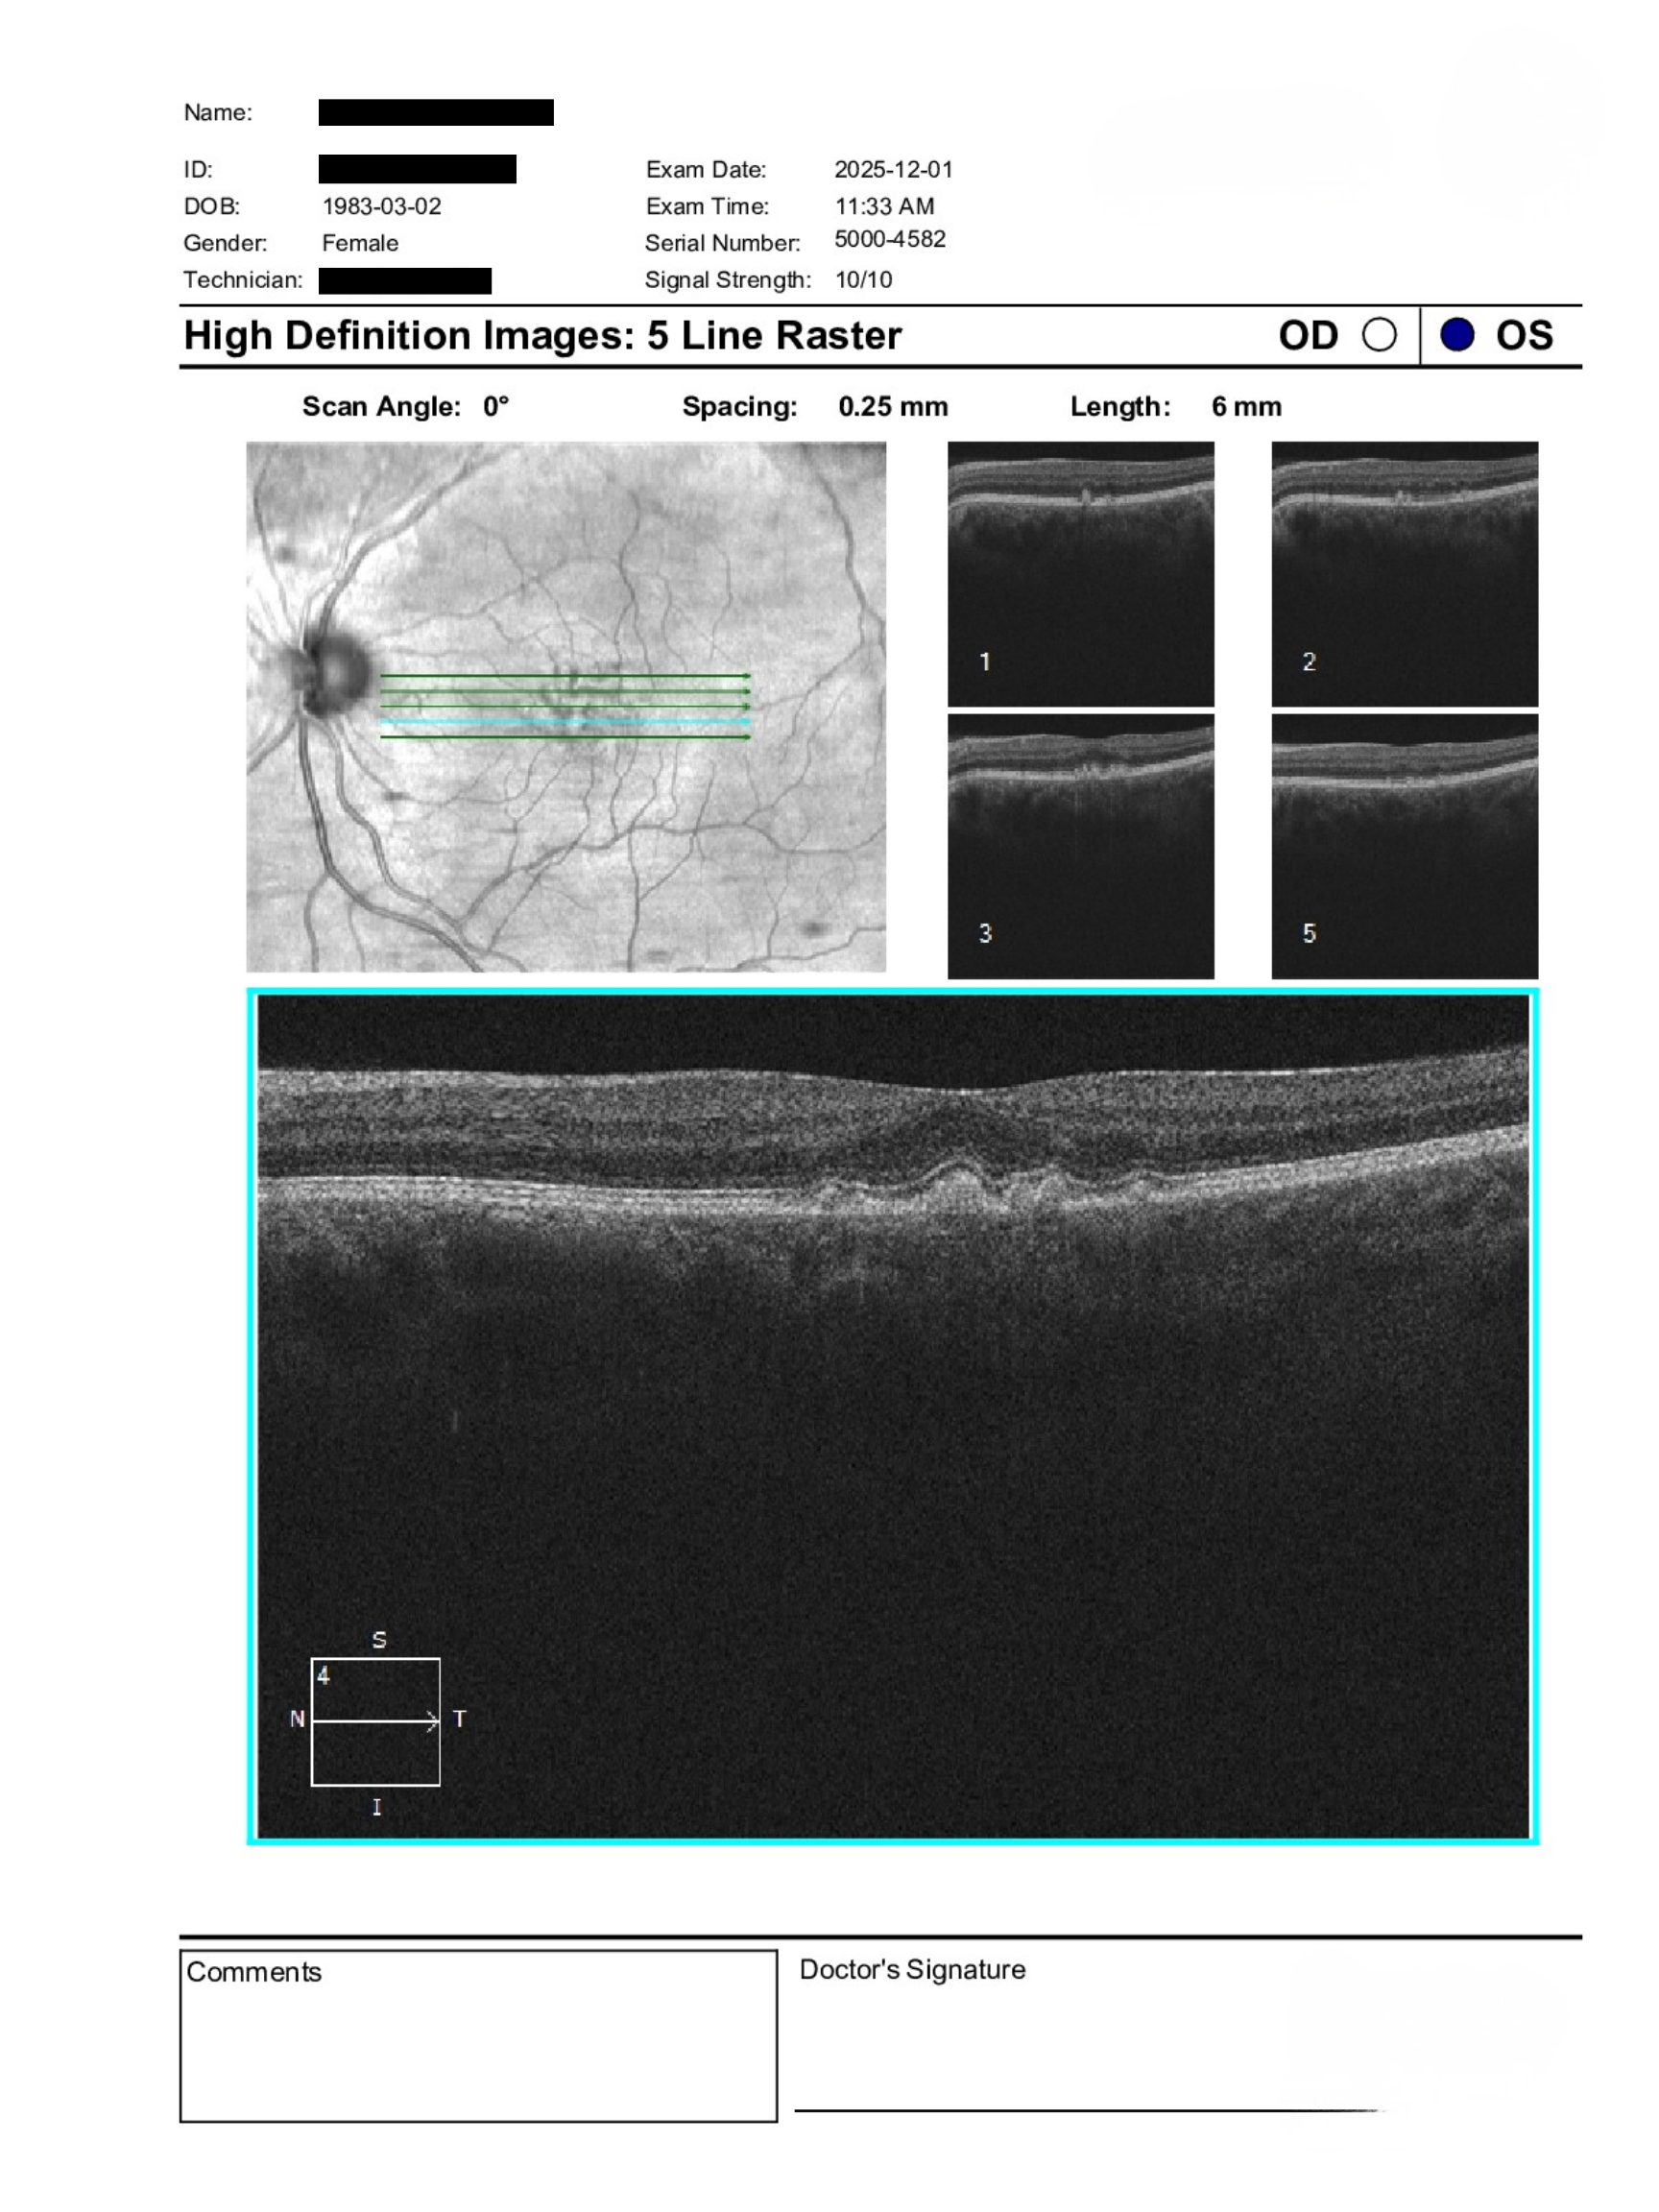

A 43-year-old patient was referred for evaluation of suspected macular dystrophy with a history of drusen and prior genetic testing suggesting possible retinal associations. BCVA is 20/20 in both eyes with IOPs of 14 mmHg OD and 16 mmHg OS. Anterior segment examination is unremarkable aside from trace nuclear sclerosis. Posterior segment shows bilateral drusen with otherwise healthy discs, vasculature, and peripheral retina. OCT imaging was performed to further assess macular structure.

Findings are most consistent with a pattern dystrophy given the patient’s age and imaging features. These conditions may have a genetic component, though routine genetic testing is not typically required unless there are systemic associations, progressive vision loss, or clear signs of inherited retinal disease such as photoreceptor disruption.

Pattern dystrophies can overlap with other inherited or metabolic syndromes, but many cases remain stable with good visual function. Referral for genetic evaluation is optional and should be guided by patient interest and clinical progression. Ongoing monitoring is appropriate, with consideration for in-person ophthalmology assessment if changes develop.

Pattern dystrophies are a group of inherited macular disorders characterized by pigment deposition at the level of the retinal pigment epithelium. They often present in mid-adulthood and may mimic age-related macular degeneration on clinical exam. Visual prognosis is generally good, though slow progression can occur over time.